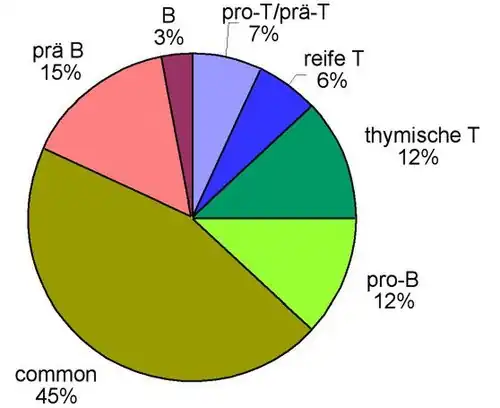

Entscheidend ist die Immunphänotypisierung der aus dem Blut oder mittels Knochenmarkpunktion gewonnenen Leukämiezellen, die heute meist mit mittels Durchflusszytometrie (FACS = Fluorescence activated cell sorting) erfolgt. Damit wird untersucht, ob und in welchem Ausmaß sich bestimmte Proteine an der Oberfläche oder im Zytoplasma der Zellen befinden. Das Expressionsmuster verschiedener lymphatischer, myeloischer und Vorläuferzell-Antigene ermöglicht die Zuordnung zu B- oder T-Zellreihe und die Festlegung des Differenzierungsstadiums. Man kann die ALL dementsprechend als B-Linien-ALL (mit B-lymphozytärer Differenzierung, weiter unterteilbar in „B-Vorläufer-ALL“ und „reif(zellig)e B-ALL“) oder T-Linien-ALL (mit T-lymphozytärer Differenzierung, weiter unterteilbar in „T-Vorläufer-ALL“ und „reife T-ALL“) einordnen. Die Tabelle unten zeigt die Einteilung der akuten lymphatischen Leukämie aufgrund des Oberflächen-Antigenmusters nach der sogenannten EGIL-Klassifikation (EGIL = European Group for the Immunological Characterization of Leukemias).[6] Die ALL-Zellen werden dabei nach ihrem „Reifungsgrad“ eingeteilt, d. h. eine pro-B-ALL ist eine ganz unreife Form, dann kommt die common ALL, gefolgt von der prä-B-ALL. Die reife B-ALL zeigt in ihrem Antigenmuster schon viele Merkmale reifer B-Lymphozyten. Analog ist es bei der T-Reihe: pro-T → prä-T → thymische (corticale) T → reife T. Etwa 75 % der ALLs im Erwachsenenalter lassen sich der B-lymphozytären Reihe zuordnen und etwa 25 % der T-lymphozytären Reihe. Bei ALL im Kindes- und Jugendalter beträgt das Verhältnis etwa 85 % : 15 %.